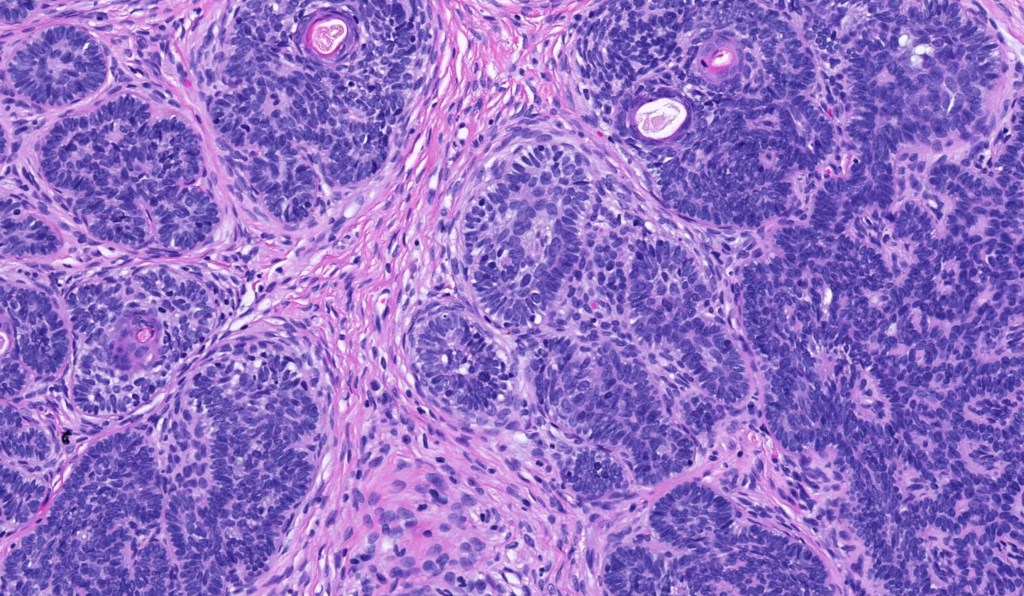

Histological features

•The classical appearance consists of keratocysts & lobules of basaloid cells

•Some tumors are devoid of keratocysts

•Variable continuity with the epidermis

•Basaloid lobules show peripheral palisading

•Retraction artifact and mucin deposition as seen in BCC are not present

•Mitoses & apoptosis may be present

•Perifollicular mesenchyme is always conspicuous and sometimes densely aggregated are seen indenting the baslaloid lobules (papillary mesenchymal bodies)

•Narrow epithelial strands arising from the basaloid lobules are often present

•Amyloid, foreign body granuloma formation to free keratin & calcification are variable features